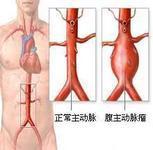

腹主动脉瘤

628健康网为您分享有关腹主动脉瘤的症状,腹主动脉瘤的治疗方法,腹主动脉瘤的预防知识,腹主动脉瘤的症状图片,腹主动脉瘤...